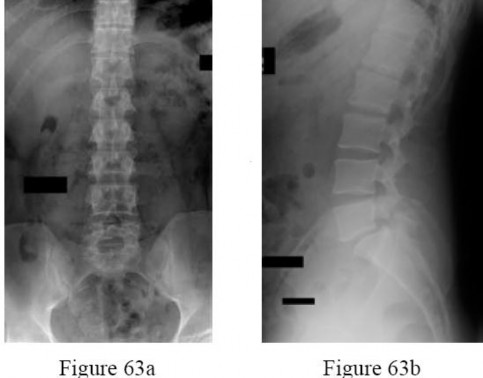

A 22-year-old male requires the placement of a halo vest for a complex upper cervical spine injury.

Where is the correct anatomical "safe zone" for the placement of the anterior halo pins in an adult?

Explanation